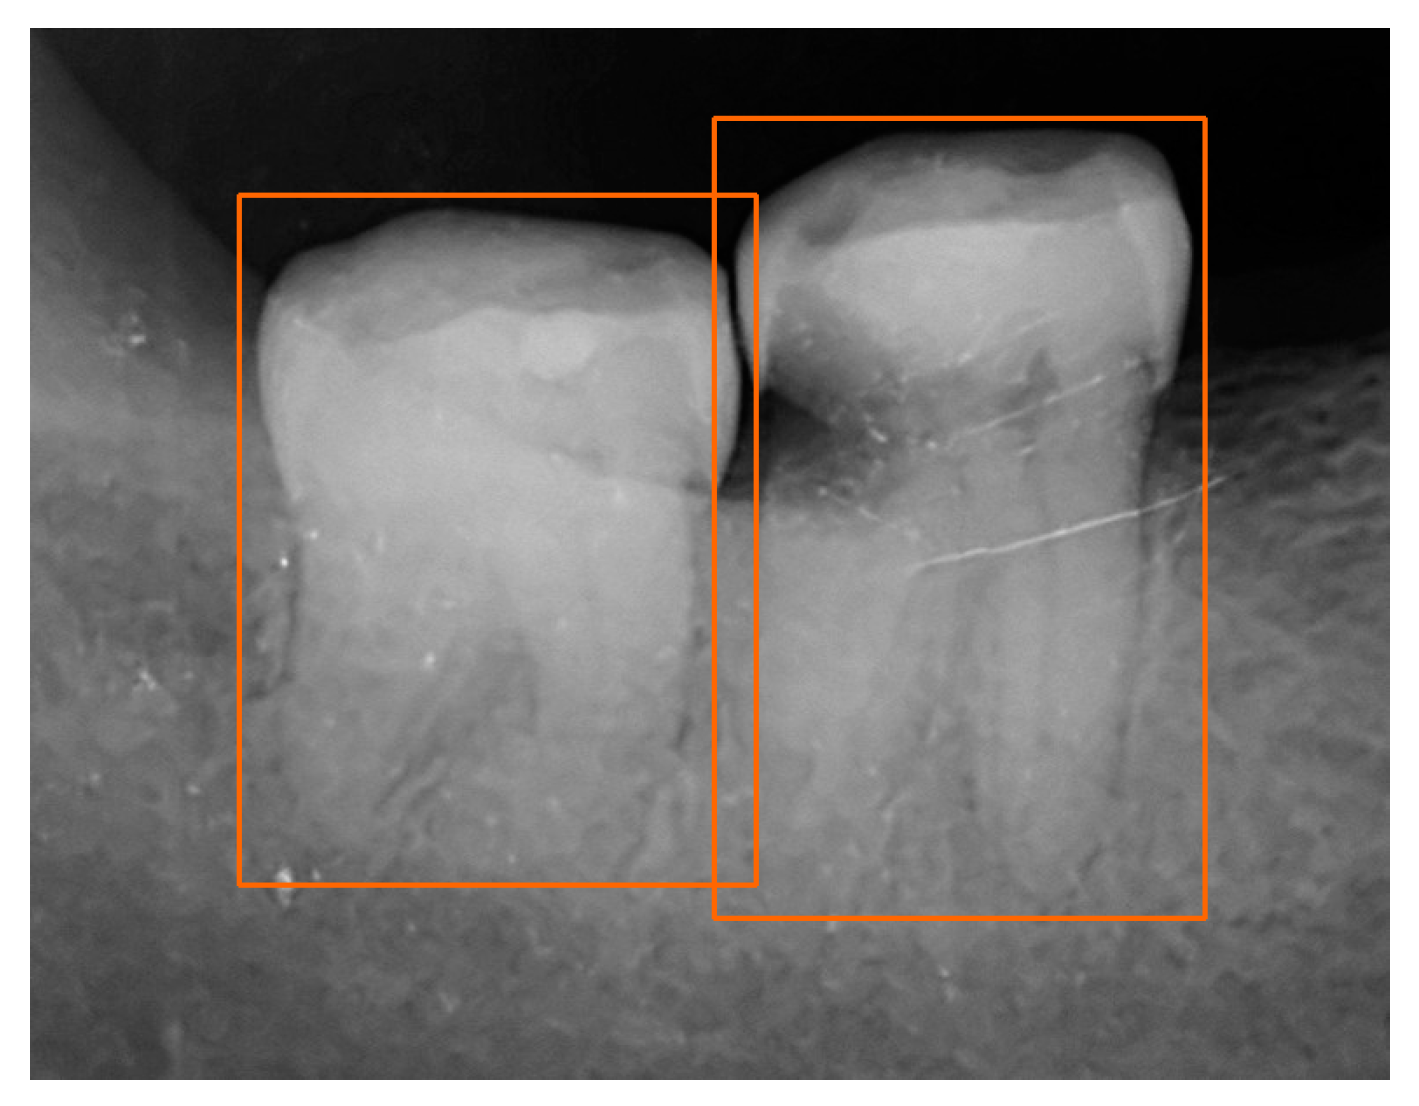

Deep Learning-Based Recognition of Periodontitis and Dental Caries in Dental X-ray Images

2.1. Dataset